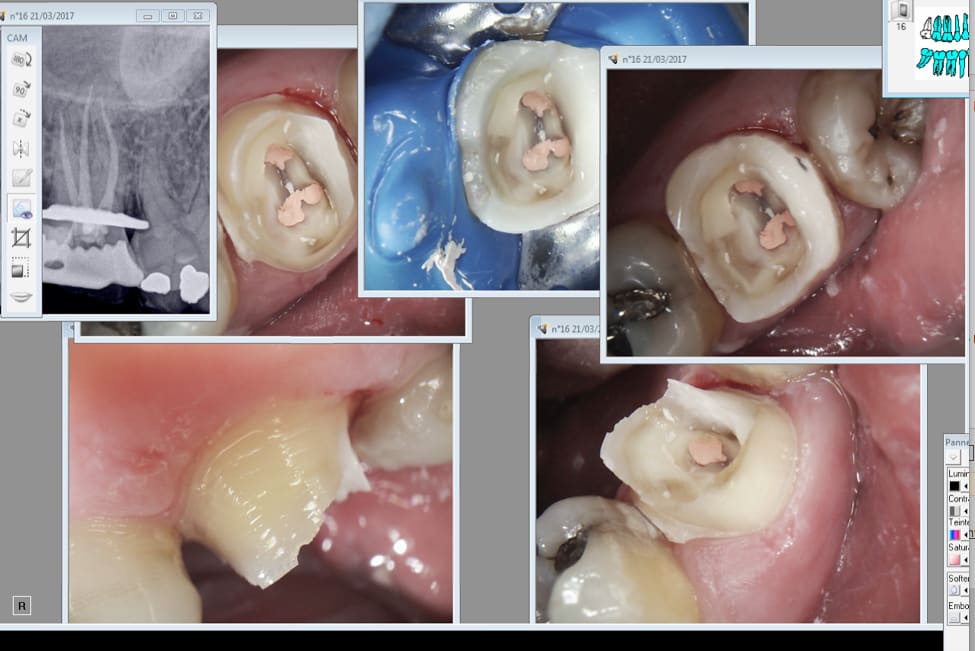

> Je suis dans l'indication de l'onlay si j'estime que la pulpe n'est pas nase,

> je

> suis dans l'indication de l'endo si j'estime le contraire. Enfin pour le SC33

> ou

> l'ic la décision se prend après préparation périphérique. Au vu de ces photos

> tu

> en penses quoi ? Et encore la moitié qui reste c'est ma reconstitution pré

> > endo. D'ailleurs il en reste un peu en distal après prépa de l'ic ca colle

> fort. . -)

Après préparation j'ai estimé que l'inlay core était plus indiqué. Mais tu peux penser l'inverse.

C'est quand meme costaud les collages ( tu peux appuyer fort sur les restes de la reconstitution pré endo ca ne cède pas) ca devrait etre plus indiqué je trouve . -)